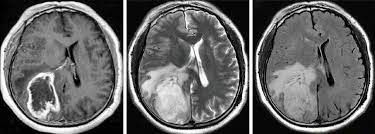

Brain tumors constitute 1.5% of all the cases of cancer. Individual with brain tumor may present with one or more of the following cardinal clinical feature: 1. seizures 2. focal neurological deficits 3. raised intracranial pressure Reference: Bailey and Love's Short Practice of Surgery Image via: https://www.uib.no/en/btrc/101032/primary-brain-tumours